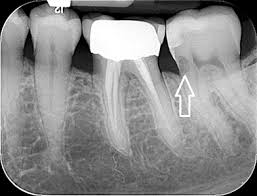

External root resorption treatment. If a dentist is able to spot the external symptoms and remove the cells causing damage in time you may not require any further dental care. Root resorption has been defined as the loss of dental hard tissue as a result of osteoclastic cell action 1 and can occur on both external and internal surfaces. If you can access then treatment with geristore or similar and possibly TCA for 1-4 minutes to remove tissue fragments.

The therapeutic measures which can regulate clastic activity include endodontic treatment the use of specific anticlastic agents such as Ledermix paste non-specific necrobiotic agents such as calcium hydroxide and trichloracetic acid surgery or root surface conditioners. External root resorptions are processes in which the loss of cementoblasts occurs causing the mineralized surfaces to be susceptible to the action of clastic cells. If you look at the tooth from the coronal view youll notice the location of the resorption is a little improved making it easy to understand why we call it external cervical resorption.

However if more of the tooth structure has been affected a filling or root canal therapy might be the treatment of choice. Although it is predominantly detected by radiography in some cases root resorption may be identified by clinical symptoms such as pain swelling and mobility of the tooth. Patient was willing to try to save the tooth and took the second option. Sometimes it may be possible to repair the damage to the tooth but in some cases the only solution is to extract the. A second opinion may be necessary. In cases where the resorptive process is already established root canal treatment can arrest the resorption and encourage hard tissue repair. External root resorptions are processes in which the loss of cementoblasts occurs causing the mineralized surfaces to be susceptible to the action of clastic cells. External resorption can be misdiagnosed. External cervical resorption treatment options vary depending on the severity of the situation.

External Resorption Treatment ConsiderationsPrognosis Favorable Questionable Unfavorable External Resorption Minimal loss of tooth structure Located cervically but above the crestal bone The lesion is accessible for repair Apical root resorption associated with a tooth exhibiting pulp necrosis and apical pathosis Minimal impact on restorability of tooth. What is the treatment for dental resorption. The therapeutic measures which can regulate clastic activity include endodontic treatment the use of specific anticlastic agents such as Ledermix paste non-specific necrobiotic agents such as calcium hydroxide and trichloracetic acid surgery or root surface conditioners. If you look at the tooth from the coronal view youll notice the location of the resorption is a little improved making it easy to understand why we call it external cervical resorption. If a dentist is able to spot the external symptoms and remove the cells causing damage in time you may not require any further dental care. Root canal crown gum surgery tooth removal extraction. The treatment of root resorption is basically root and or periodontal endodontic treatment depending on the.